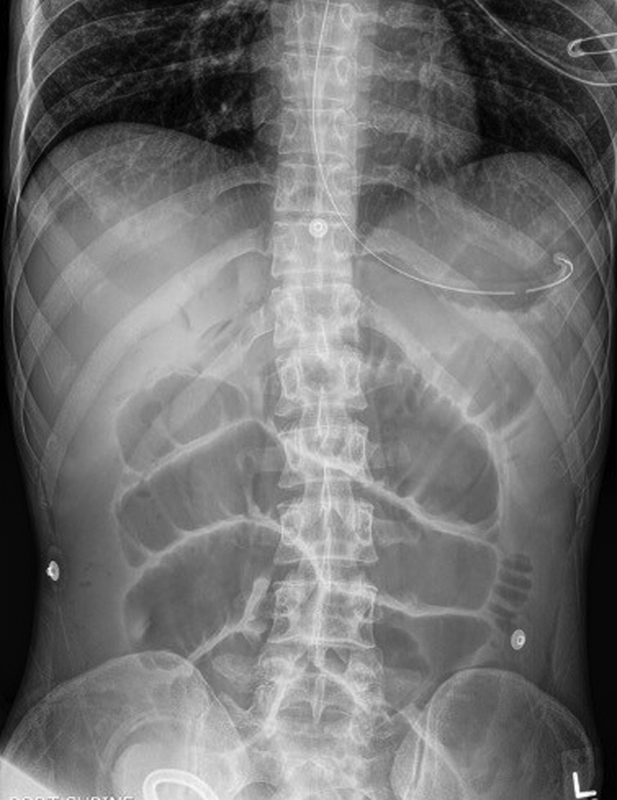

Radiographic evaluation may begin with an abdominal X-ray series which includes an upright chest, abdominal supine, and lateral decubitus radiographs. The chest X-ray can demonstrate aspiration or pneumoperitoneum, while the abdominal radiographs may show gastric distension, air-fluid levels, dilated loops of small bowel, and a paucity of colonic/rectal gas ( Fig. 1 ). Placement of a nasogastric (NG) tube for gastric decompression should be prompt in an actively vomiting patient or if there is evidence of gastric dilatation, especially in an elderly or altered patient who may not be able to effectively protect their airway.

Fig. 1.

Upright plain abdominal radiograph demonstrating air-fluid levels in the stomach and intestines ( arrows ) and dilated loops of small bowel.